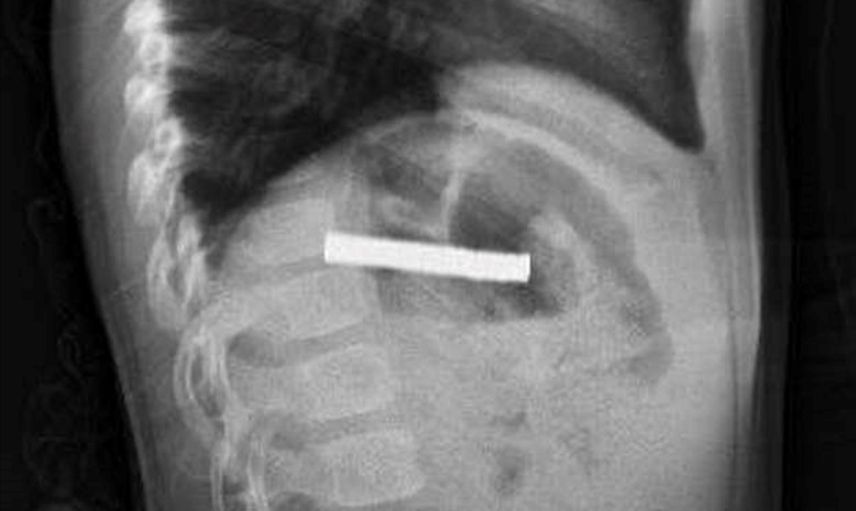

Fırat Üniversitesi Çocuk Gastroenteroloji Hepatoloji ve Beslenme Bilim Dalı Başkanı Prof. Dr. Yaşar Doğan liderliğindeki ekip, yaptığı tetkiklerde mıknatısların yemek borusunda yapışarak tıkanmaya neden olduğunu belirledi. Ekip, müdahale ederek mıknatısları başarılı bir biçimde çıkardı.

Çocuk, yapılan işlemin ardından gözlem altında tutuldu ve ailesinin isteğiyle taburcu edildi. Prof. Dr. Yaşar Doğan, "Mıknatıslar uzun süre yemek borusunda kaldığı için hasar bırakmıştı. İşlemi kolaylaştırmak için mıknatıslar mideye alındı ve mideden özel bir fileyle çıkarıldı" şeklinde bilgi verdi.